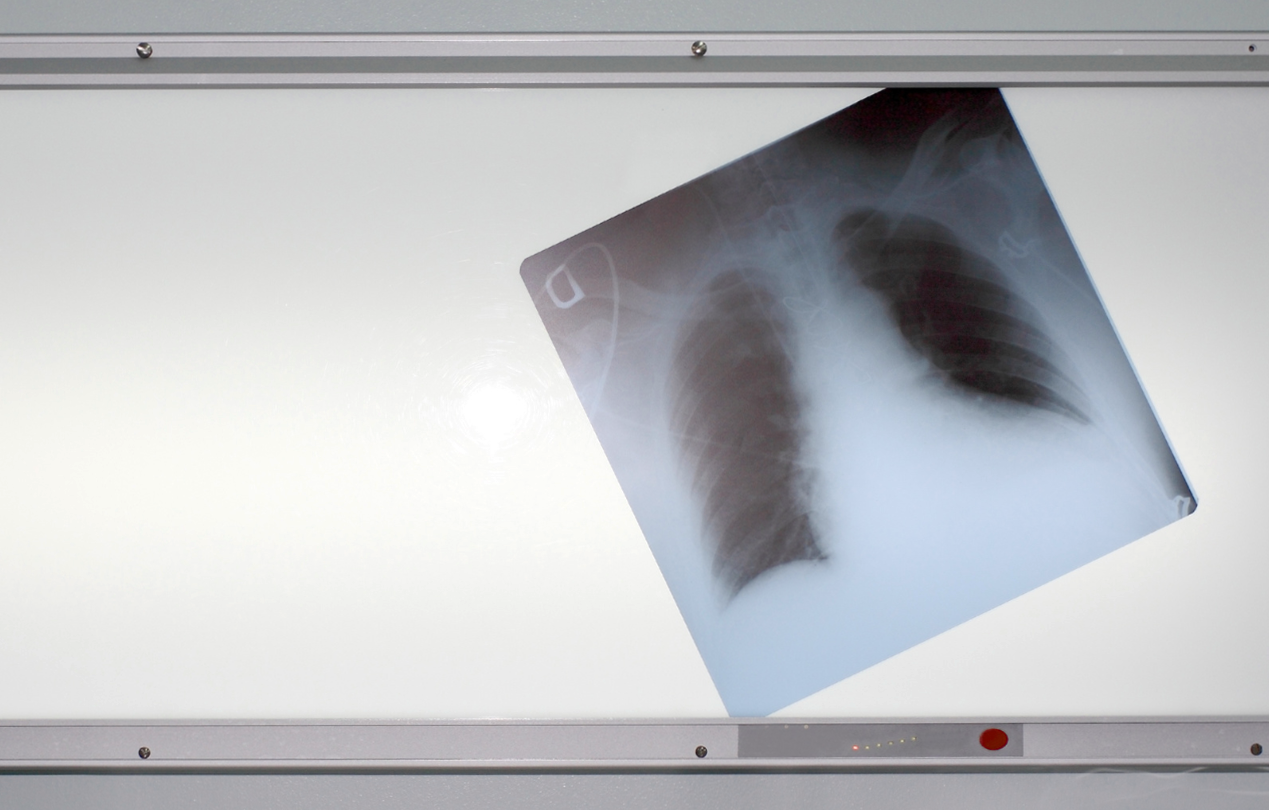

Пара слов об устройстве дыхательной системы человека. Воздух, пройдя через нос или рот, а затем через гортань, попадает в легкие через особую трубку — трахею, которая затем разветвляется на трубки поменьше — бронхи, которые и дальше разветвляются, становясь все тоньше. Сами же легкие — это не просто два «мешка», которые наполняются воздухом, в них находится множество альвеол (пузырьков), как раз и отвечающих за обмен кислорода и углекислого газа, то есть — за процесс дыхания. Большая часть дыхательных путей выстлана реснитчатым эпителием, который задерживает частички пыли, грязи и всего, что могло попасть при вдохе в трахею. В путях есть и железы, выделяющие слизь, увлажняющую поверхность дыхательных путей и задерживающую инородные тела, которые к ней прилипают. Все «пойманное» ресничками и слизью, выводится из организма во время кашля.

Вернемся к негативному воздействию курения на организм человека. Во-первых, табачный дым и смолы, вдыхаемые при курении, иссушивают слизистую дыхательных путей, нарушают работу желез, которые выделяют слизь. Из-за этого постепенно гибнут реснички. То есть дыхательные пути оказываются незащищенными от попадания в них инородных частиц. Во-вторых, смолы оседают в альвеолах, что ухудшает естественный газообмен. Соответственно, человек получает меньше кислорода, чем мог бы. В-третьих, никотин — это яд, который не только в целом негативно воздействует на организм, но еще и приводит к сужению сосудов. Это нарушает работу не только мелких капилляров, но и всей сердечно-сосудистой системы в целом, которой не нравятся такие «встряски».